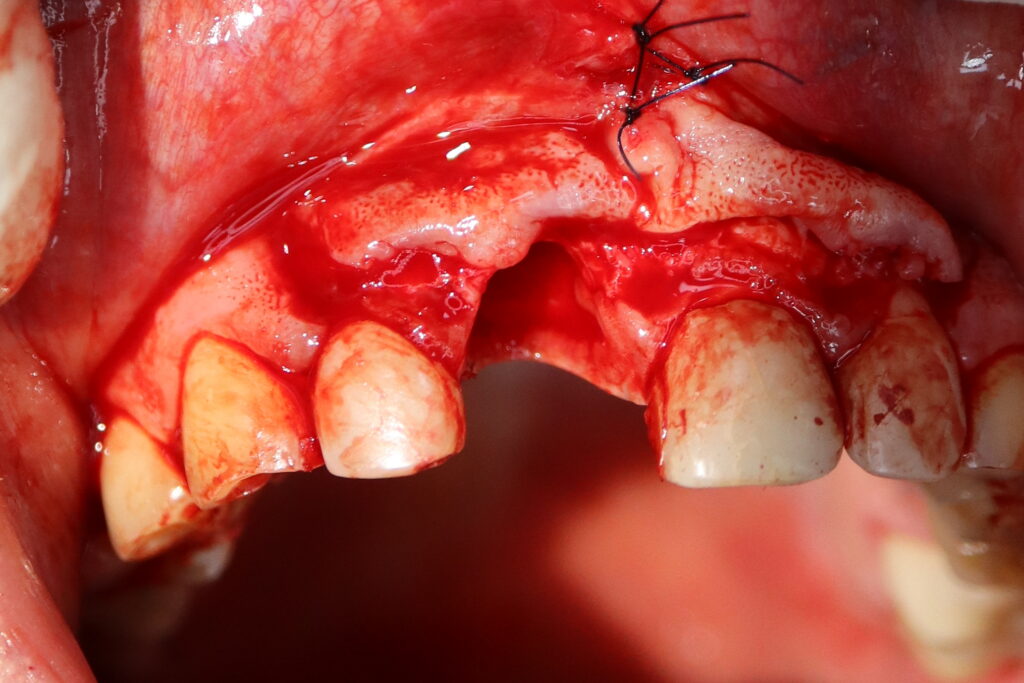

Процесс работы

Что было сделано:

Хирургом-имплантологом были проведены следующие манипуляции: удаление зуба 1.1, удаление кисты, аугментация твердых и мягких тканей в области 1.1

с применением свободного соединительнотканного трансплантата из слизистой оболочки бугра верхней челюсти, пластика уздечки верхней губы.

Установлен имплантат Straumann BLT и формирователь десны.

удаление зуба

Это фото может содержать тяжелый для восприятия контент